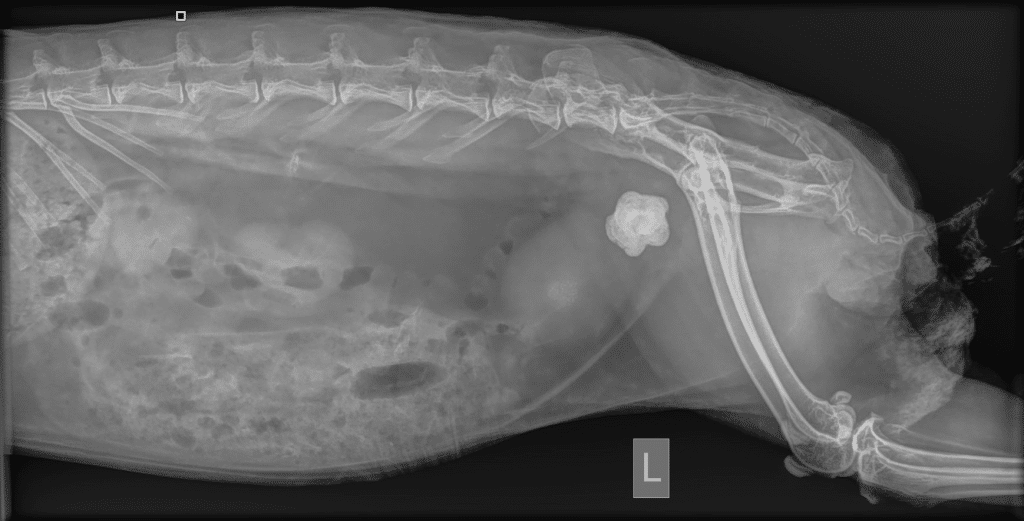

Bladder problems are very common in rabbits, and for the most part problems with urination can be due to infection or thickening of the urine to form a sand-like sludge. However, Obi’s x-rays showed he has been keeping a big secret for quite some time.

Obi’s X-Ray

Within Obi’s teeny little rabbit bladder was a massive 1.5cm rock! The bladder stone was so big, that looking at the x-ray, you could almost miss the numerous little stones behind it.